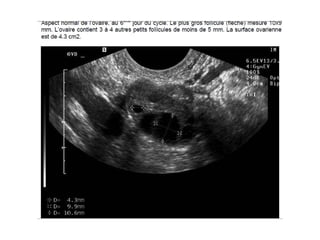

Le SOPK: Diagnostic Pas besoin de test dynamique/  Mesure de FSH, E2 (rech d’hypogonadisme hypogonadotrope devant spanio/aménorrhée), PRL? Testostérone Echo: nombre de follicules >12/ovaire, augmentation de volume  des ovaires(>10ml) Attention: première partie de cycle, opérateur dépendant.  Nouveau marqueur? AMH

Le SOPK: DiagnosticPas besoin de test dynamique/ Mesure de FSH, E2 (rech d’hypogonadisme hypogonadotrope devant spanio/aménorrhée), PRL? Testostérone Echo: nombre de follicules >12/ovaire, augmentation de volume des ovaires(>10ml) Attention: première partie de cycle, opérateur dépendant. Nouveau marqueur? AMH